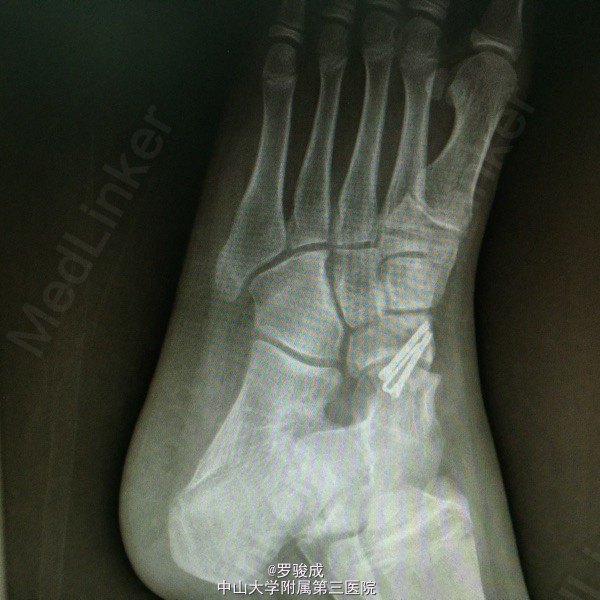

左足内侧疼痛2年余 两年余前运动后出现左足内侧疼痛,伴胀痛,无放射痛,无足部麻木。近来症状加重,遂前来我院就诊,X线提示左足副舟骨综合症。

左足内侧弓副舟骨表面硬性突起,无红肿,皮肤温度无升高,压痛明显。左足神经血运及感觉良好

诊断为左足副舟骨综合症。 行左足副舟骨清理融合术

足副舟骨综合症是一种先天性疾病,是舟骨结节部第二化骨中心的先天异常,在舟骨结节处形成一个独立的副骨。 足内侧隆起,久站或行走较长时, 感足底内侧疼痛。